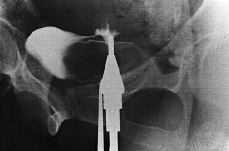

Para el diagnóstico sepracticó fundamentalmente cistoscopia yuretrocistografía o histerosalpingografía, aunque enla paciente 6 se precisaron otras exploraciones complementariascomo urografía intravenosa, TAC, enema opaco ytránsito gastroduodenal (Figs. 1 y2). A pesar de todo en esta paciente no se llegó aldiagnóstico de una fístula vesicocervical sobrecérvix restante posthisterectomía subtotal hasta elmomento de la intervención quirúrgica, con posteriorconfirmación en la anatomía patológica alobservarse la presencia de glándulas endometriales incluidasen la pared vesical

Figura1. Histerosalpingografía en la que se observa el paso decontraste a la vejiga.